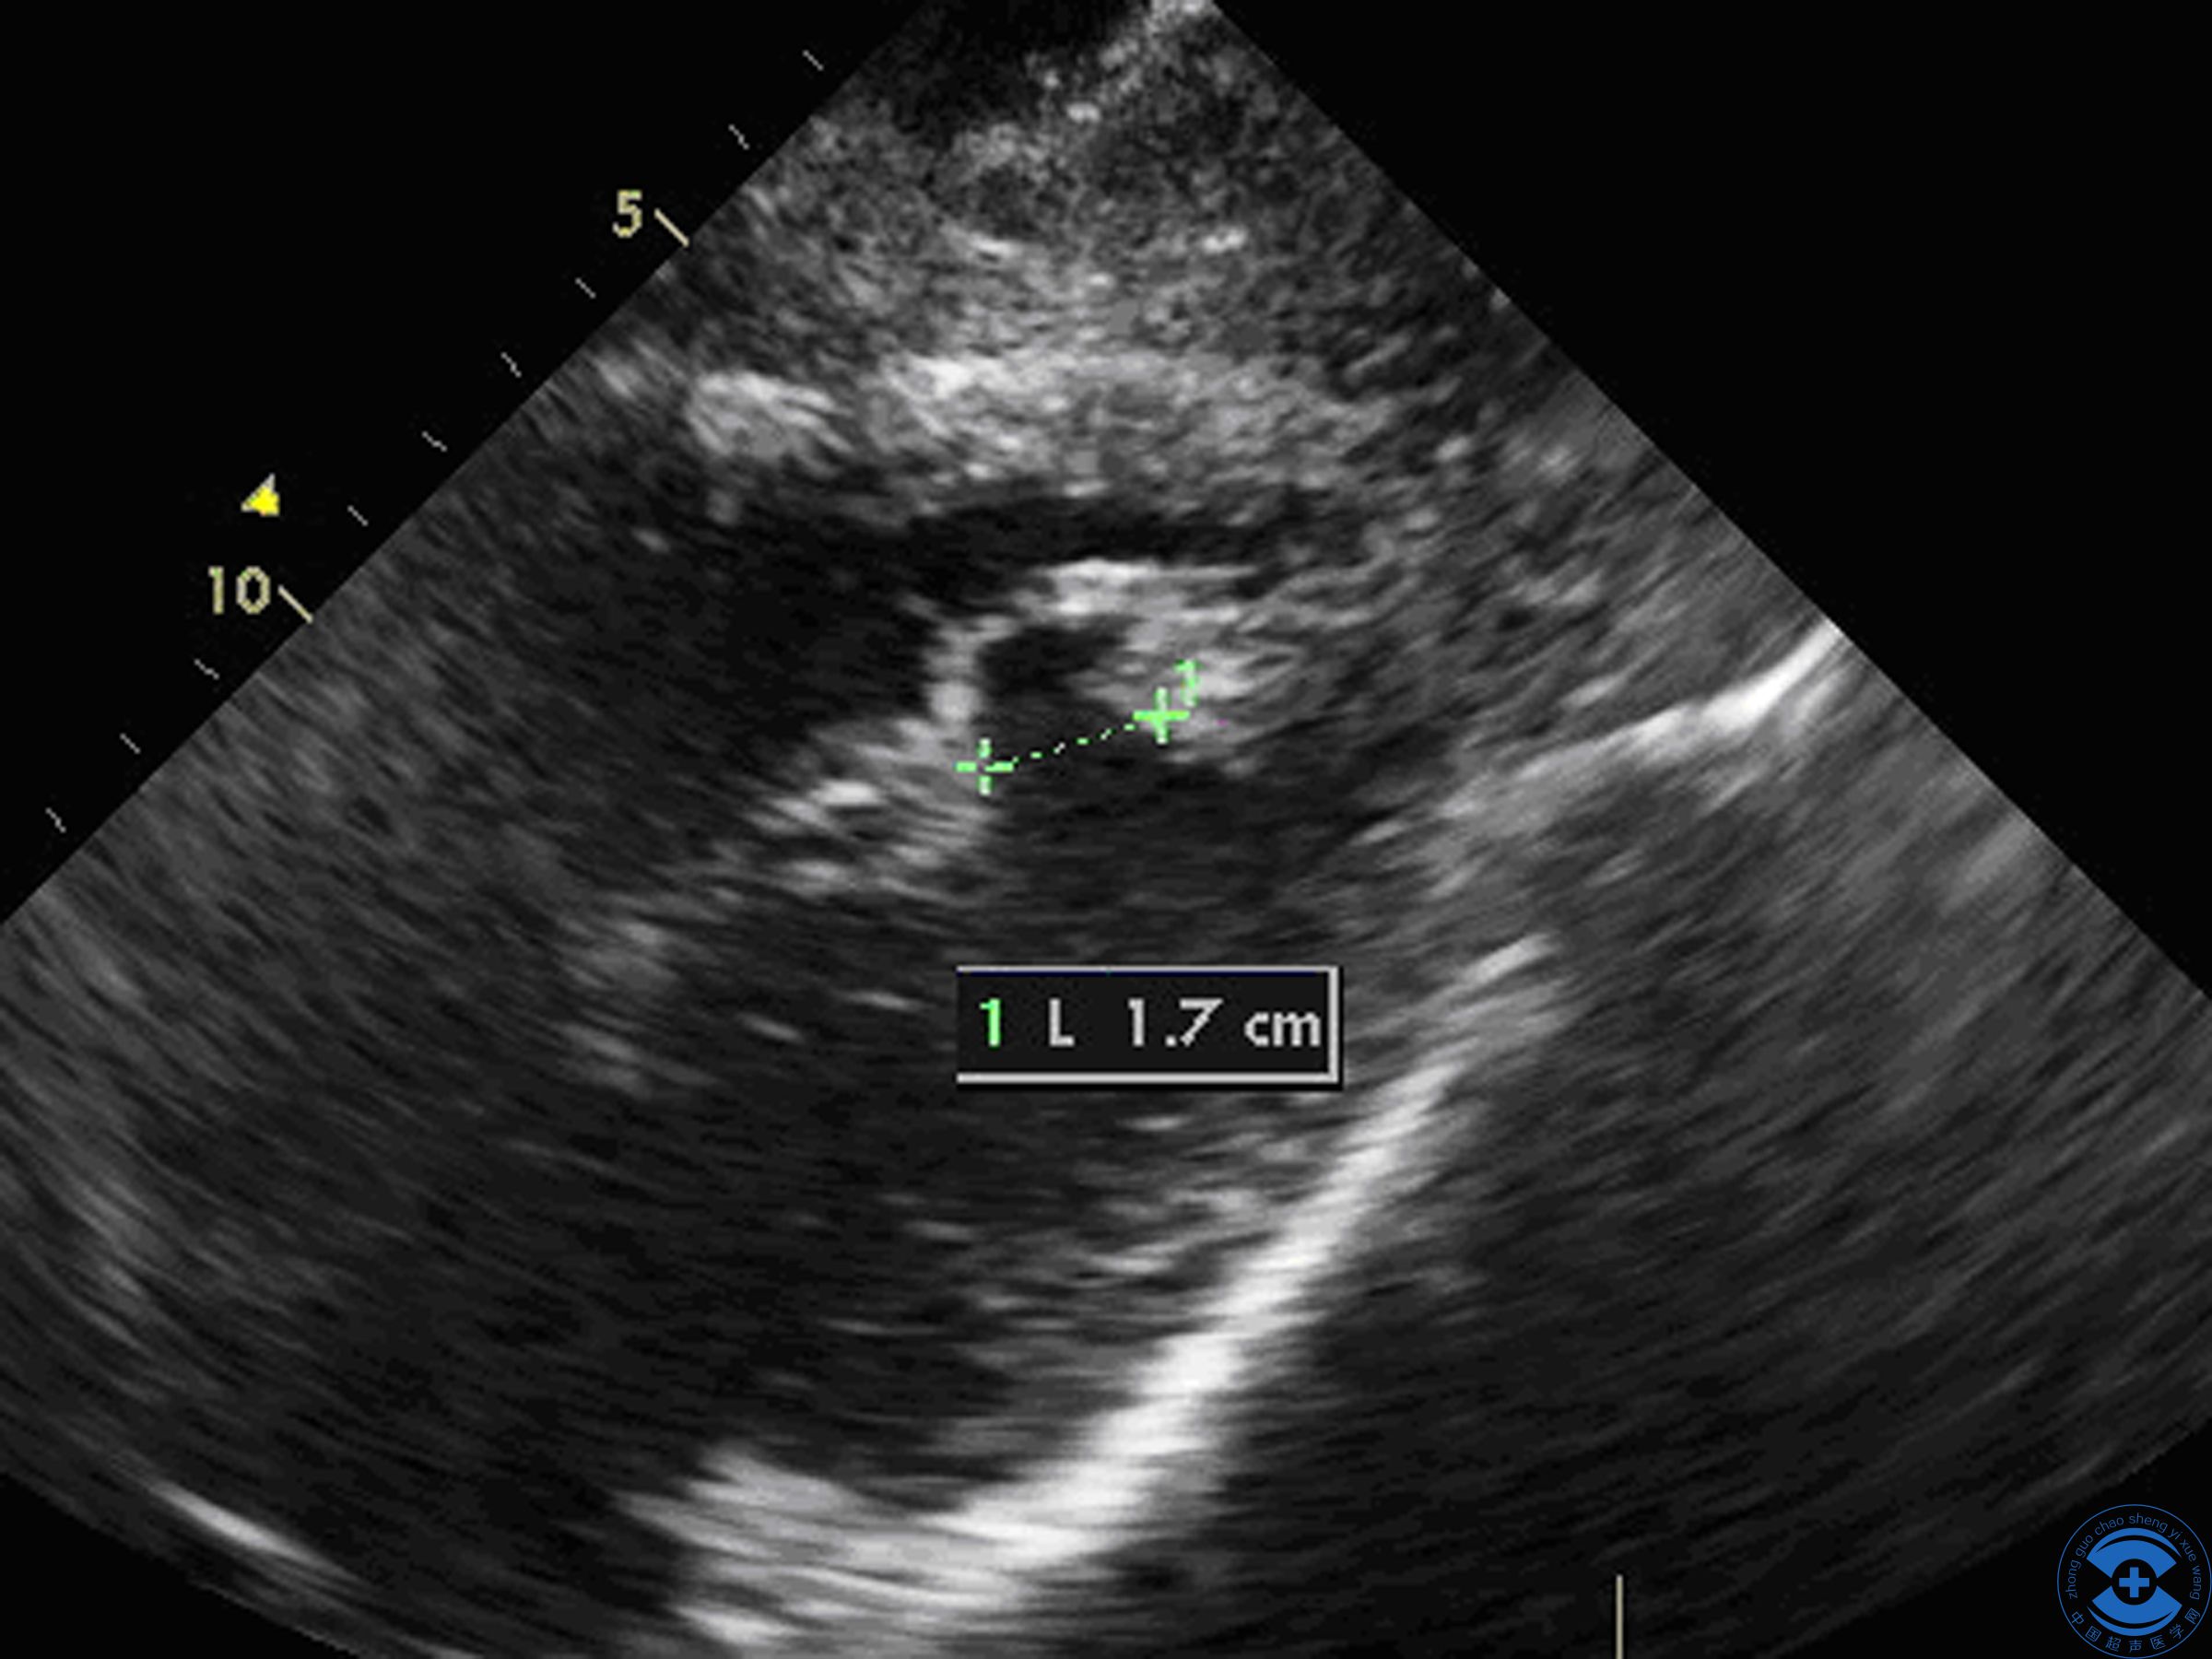

图1 后间隔心尖段回声中断:剑突下四腔心切面见后间隔心尖段回声中断,左室面中断约